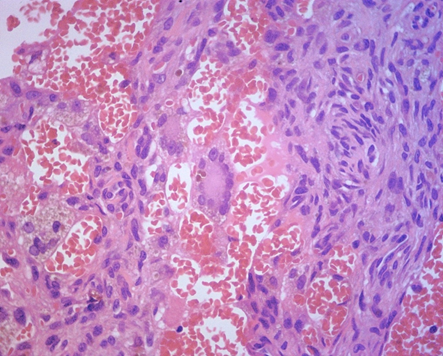

Figure 5&6 fibrohistiocytoid neoplasia, with giant cells containing brownish pigmentation suggestive of hemosiderin, cracks without vascular endothelium, containing red blood cells inside.